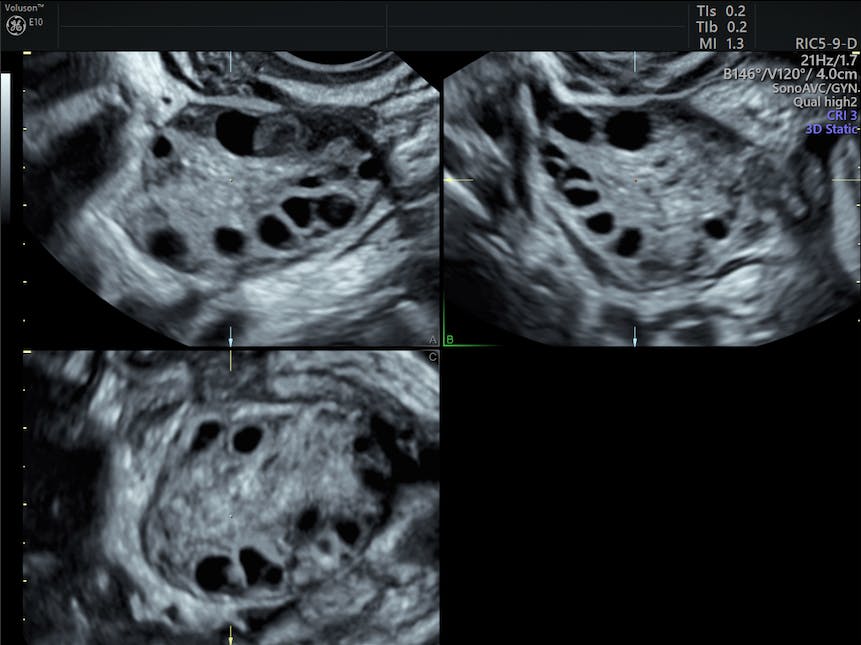

Bilateral Polycystic Ovaries Ultrasound

Bilateral polycystic ovaries ultrasound. On an ultrasound image inset a polycystic ovary shows many follicles. Ultrasound ovaries may be normal in pcos and conversely polycystic ovarian morphology pcom may be seen in women without the syndrome. Each dark circle on the ultrasound image represents a fluid filled follicle in the ovary. Polycystic ovary syndrome is usually associated with bilateral enlarged ovaries studded with atretic follicles not with cysts.

It has been reported that ovaries can develop a polycystic morphology over time and enlarged ovaries with a polycystic appearance can subsequently become normal in size. Polycystic ovaries may be seen in 20 women of reproductive age 1 4. However it is well accepted that women with pcos tend to have larger ovaries with an increased number of follicles. Your doctor may suspect pcos if you have 20 or more follicles in each ovary.